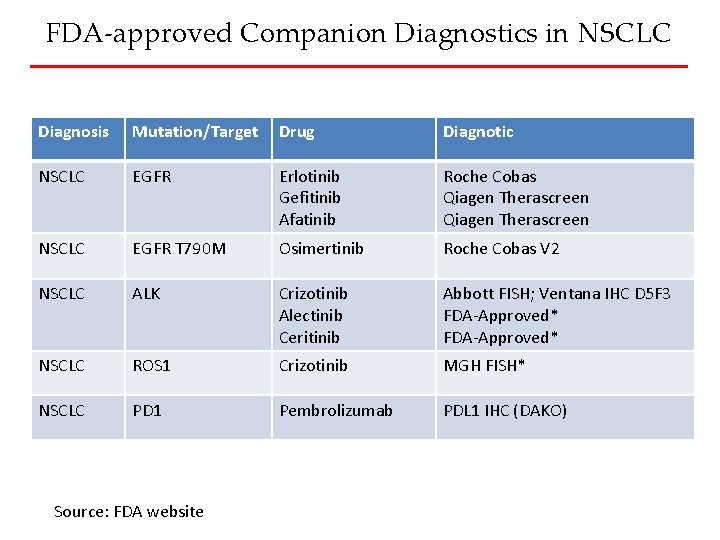

FDA-approved Companion Diagnostics in NSCLC Diagnosis Mutation/Target Drug Diagnotic NSCLC EGFR Erlotinib Gefitinib Afatinib Roche Cobas Qiagen Therascreen NSCLC EGFR T 790 M Osimertinib Roche Cobas V 2 NSCLC ALK Crizotinib Alectinib Ceritinib Abbott FISH; Ventana IHC D 5 F 3 FDA-Approved* NSCLC ROS 1 Crizotinib MGH FISH* NSCLC PD 1 Pembrolizumab PDL 1 IHC (DAKO) Source: FDA website